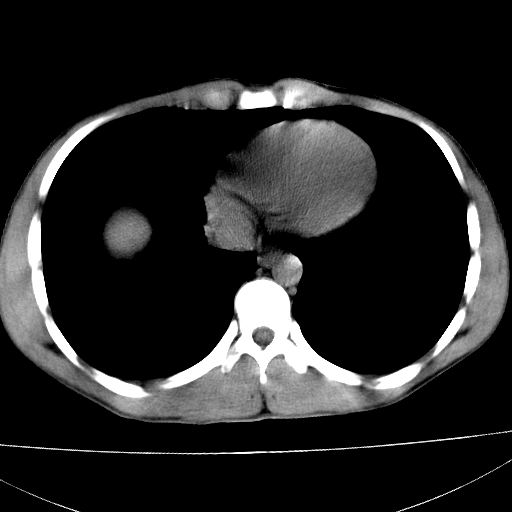

标题: CT15860:男,21岁,腹部外伤2小时伴胸疼。 [打印本页]

标题: CT15860:男,21岁,腹部外伤2小时伴胸疼。

b超示:肝破裂。

肝脏及肾脏明显有损伤性改变并激发腹腔内积液(血),以肝脏撕裂及肾周积血显著。

1)肝破裂伴腹腔积液(血)。2)右肾破裂伴右肾包膜下及肾周血肿。3)腹部空腔脏器穿孔可能。4)右侧少量胸腔积液(血)。